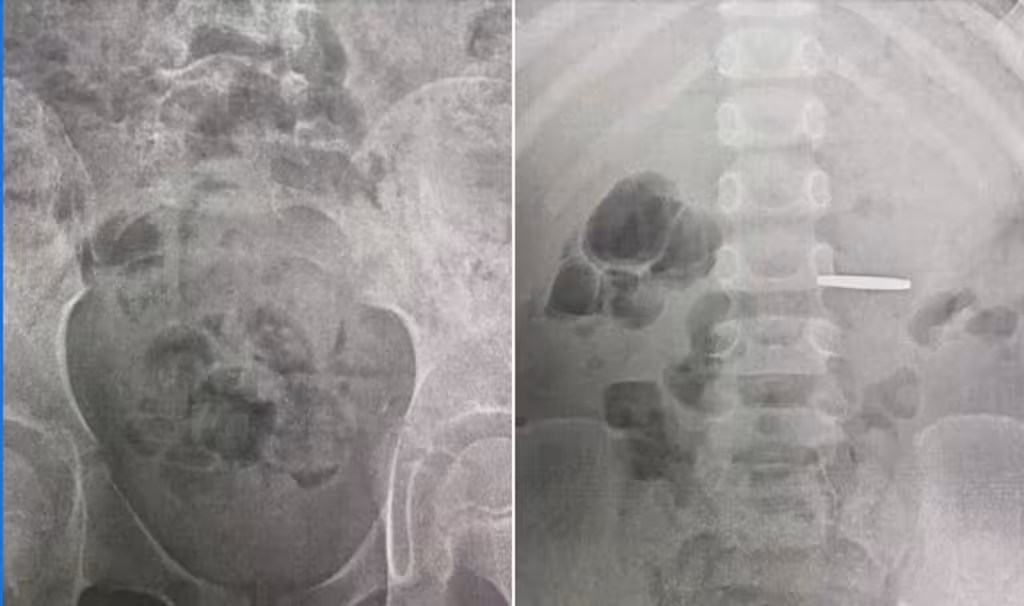

Не встигли монетки висохнути, як «швидка» доставила ще одного хлопчика, який проковтнув монету. Цього разу — 3-річний хлопчик.

У нього копійка замаскувалася майстерніше — вона потрапила у пілорус (клапан), він притиснув монету і не відпускав.

Крім того, їжа у шлунку весь час заважала лікарці дістати стороннє тіло. Але Марту Володимирівну не проведеш! Кілька обережних спроб — і 50 копійок уже назовні!